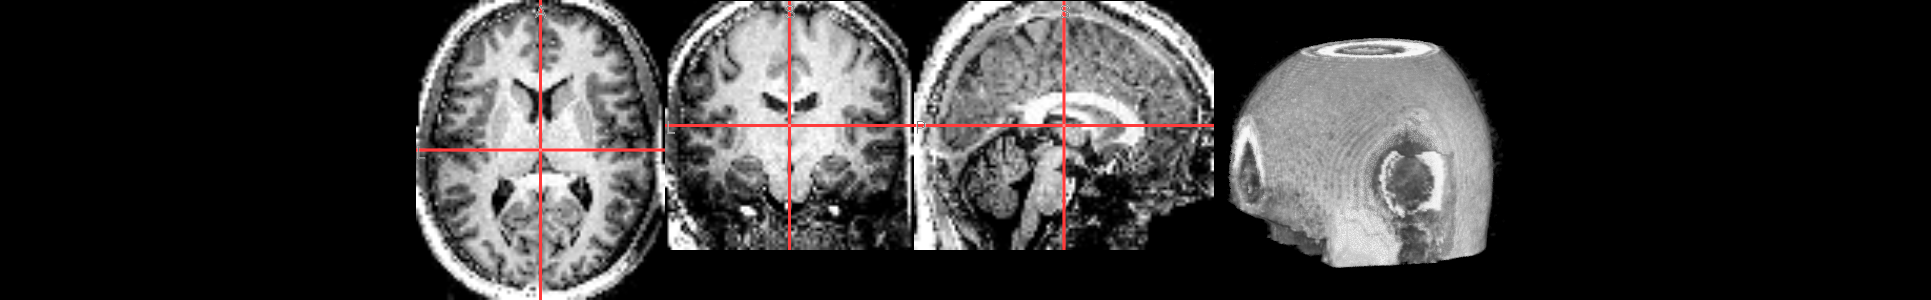

from ipyniivue import NiiVue

nv = NiiVue()

nv.load_volumes([{"path": "./sub-01_ses-01_7T_T1w_defaced_brain.nii.gz"}])

nv

from IPython.display import Image

Image(url='https://raw.githubusercontent.com/NeuroDesk/example-notebooks/refs/heads/main/books/images/sub-01_ses-01_7T_T1w_defaced_brain.png')